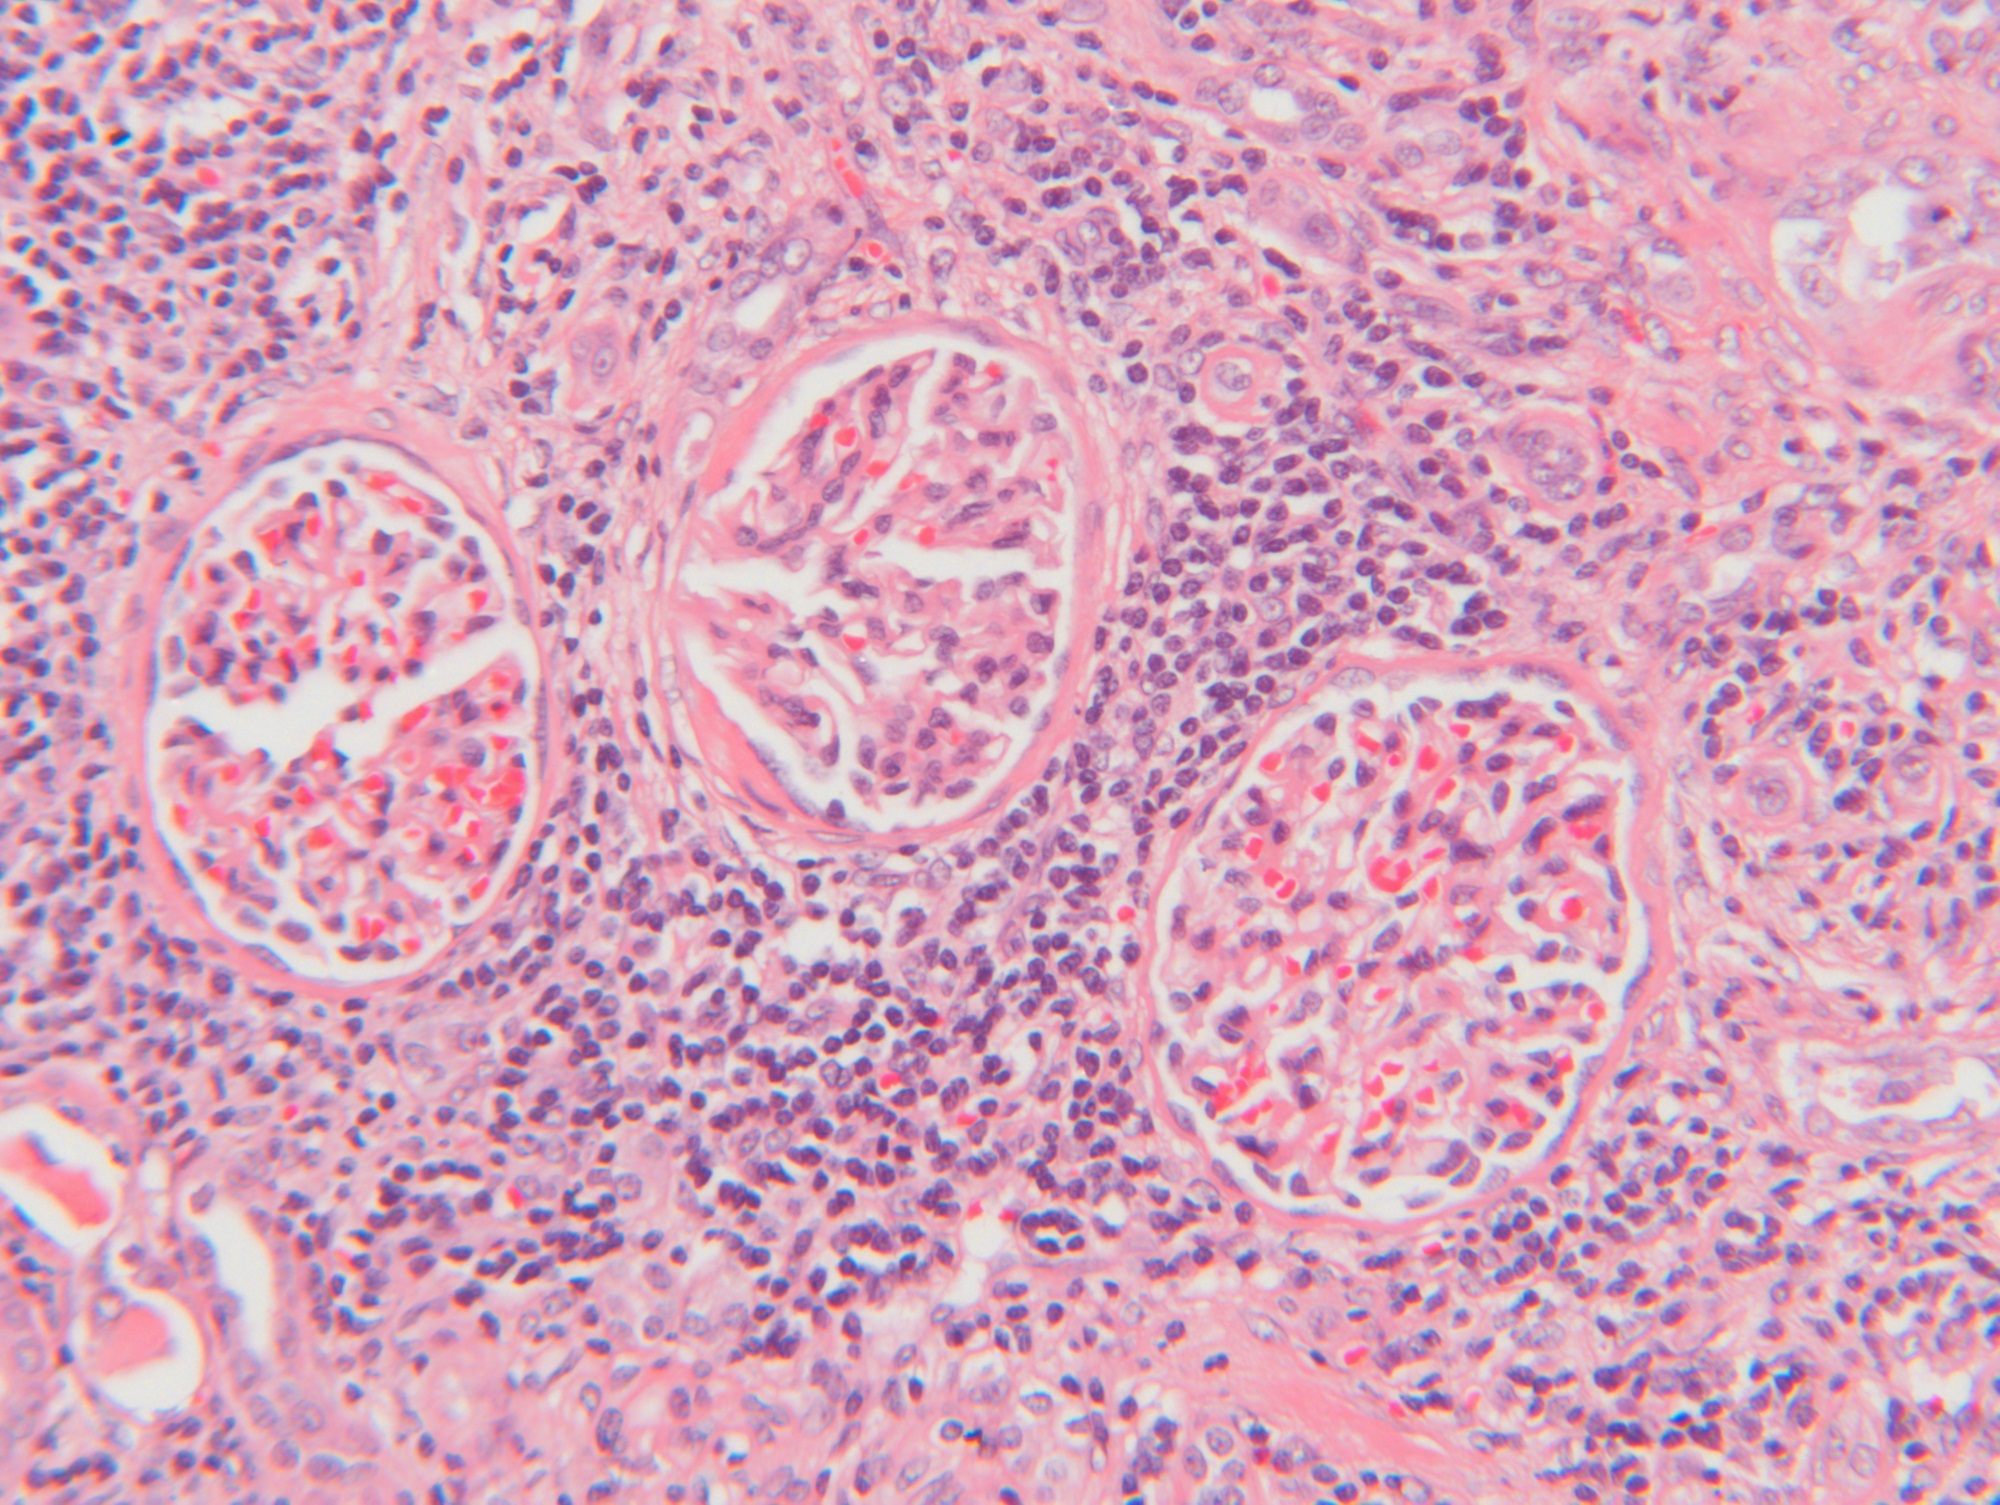

신우신염은 신장과 신우라는 부위에 염증이 생기는 질환입니다. 신장은 소변을 만드는 장기이고, 신우는 소변이 모이는 곳입니다.

신우신염은 주로 세균 감염에 의해 발생하며, 방광이나 요도에서 신장으로 세균이 거슬러 올라가는 경우가 많습니다. 신우신염은 급성과 만성으로 나눌 수 있습니다.